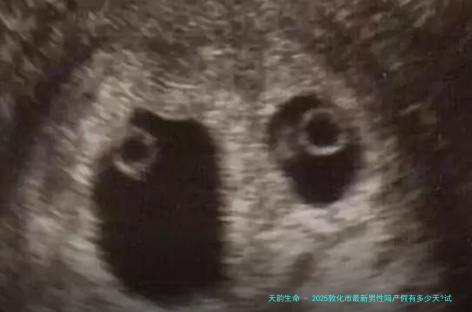

关于通过试管婴儿技术生育的情况,女性的产假会有所增多。详细而言,试管婴儿的产妇除了享受常规的九十八天产假外,还可以额定获取一个月的产假。这就是意味着,通过试管婴儿技术生育的女性共计可以享乐一百二十八天的产假。这一项策略的目的是斟酌到试管婴儿过程当中的特别之处和可能增加的身体痊愈需求。

另外,关于双胎或多胞胎的出生,每多1个婴儿,产假又会再增加半个月。比方,如若一双夫妻通过试管婴儿技术成功诞生双胎,哪样产妇将享受143天的产假(一百二十八天基础产假加之半个月的双胎额定产假)。

在医疗保障方向,敦化市也增强了对试管婴儿技术的支持强弱程度。市内诸多家医院建立了特意的辅助生殖医学中心,配置了先进设备和技术威力力,为有须要的家庭提供质量高的医护服务。政权机关还推出了多个项目贴补策略,减少病人在试管婴儿过程当中的经济承当。